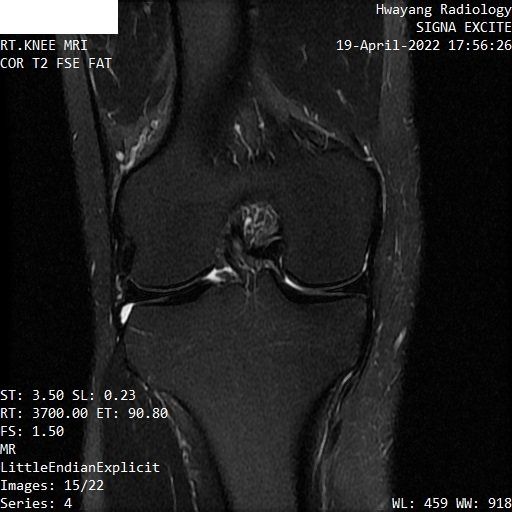

무릎연골 파열 mri좀 봐주세요 파열이 맞는지 궁금합니다.

오른쪽 무릎이 아파서 mri 찍어봤는데 집근처 병원에서 연골파열이라고 하는데

MRI 컷을 위와 같이 배열해놓은 것으로는 명확한 감별이 어렵습니다.

다만 연골부위의 MRI 상 이상 소견이 있는 것은 사실입니다.